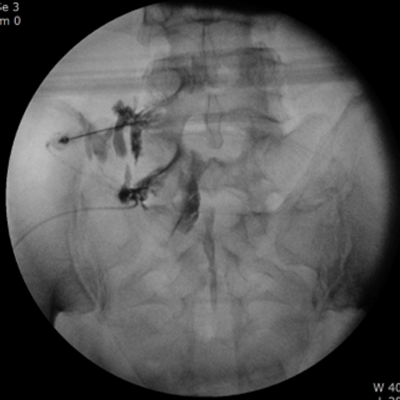

실시간 방사선 영상장치(C-arm)와 정밀 초음파(Ultrasonography)를 이용하여 통증의 원인이 되는 부위에 얇고 가는 바늘로 약물을 주입하여 통증을 완화시켜주는 치료입니다.

• 실시간으로 영상장치를 보며 시술하기 때문에 정밀도가 높고 안전함